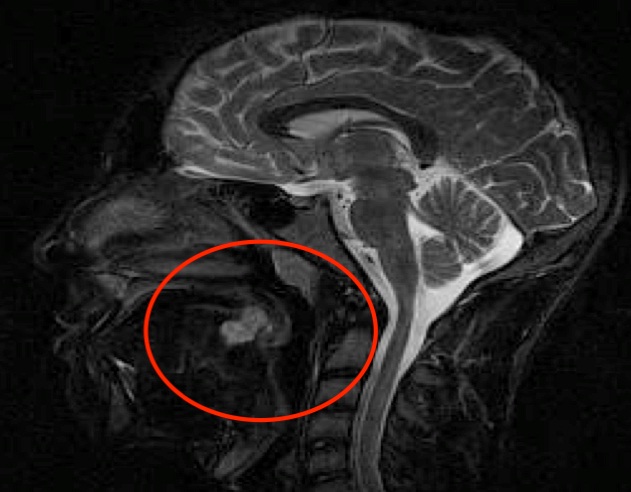

Durante la mia breve frequentazione in Pronto Soccorso, tra la moltitudine dei bambini che vi accedono per virosi, traumi e ferite, si presenta un ragazzo di 15 anni, Daniele. La sua storia clinica � piuttosto breve ma alquanto insolita, non solo per me che sono alle prime armi, ma anche per il medico e la specializzanda che seguono il caso. Daniele ci racconta che da circa 12 giorni � comparsa una tumefazione sul dorso della lingua e che, vista la sua rapida crescita, rende difficoltosa la deglutizione. Ci armiamo di abbassalingua per esaminare direttamente la sede da lui indicata, ma non appena il ragazzo apre la bocca appare evidente come l�abbassalingua sia superfluo: in corrispondenza della radice linguale risulta evidente una tumefazione di dimensioni approssimativamente pari a 2x1,5x2 cm, che giustifica senza dubbio la sintomatologia soggettiva riferita dal ragazzo (Figura 1). Ad occhio nudo la tumefazione presenta una mucosa rosea e integra, non si evidenziano segni di flogosi o infezione, n� sanguinamenti. Richiediamo allora una consulenza stomatologica ed un approfondimento mediante RMN che descrive la lesione come trilobata, a margini netti e regolari, localizzata nel terzo posteriore mediano della lingua; infine la biopsia risulta indispensabile per definirne la natura ed inquadrare meglio il caso (Figura 2).

Figura 2. Il referto istologico � quello di uno Schwannoma della base linguale per il quale il trattamento previsto � l�asportazione chirurgia, che viene programmata e che sar� risolutiva per Daniele. Lo Schwannoma o Neurofibroma � una neoformazione benigna che origina dalle cellule di Schwann della guaina mielinica. Nella maggior parte dei casi si tratta di una lesione singola, capsulata, a crescita lenta. Circa il 25-40% degli Schwannomi extracranici si sviluppano a partire dai tessuti molli di testa e collo, mentre rari sono quelli localizzati a livello della cavit� orale. Lo Schwannoma rappresenta circa l�1% dei tumori benigni del cavo orale e la lingua � considerata la sede pi� frequente a questo livello. La sintomatologia � legata soprattutto alle dimensioni e alla localizzazione della lesione. Il trattamento previsto � la resezione chirurgica; rare le recidive. Vista la stretta correlazione esistente con la Neurofibromatosi � sempre opportuno escludere in questi bambini la presenza della malattia con un accurato esame obiettivo, in Daniele peraltro assolutamente negativo, che vada a valutare in prima battuta il quadro cutaneo e quello oculare, tenendo poi a mente la possibile associazione qualora dovessero comparire nel prosieguo del tempo sintomi suggestivi di lesioni in altra sede.